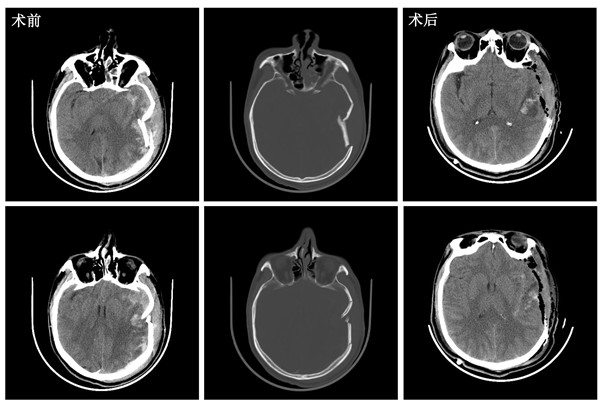

术前、术后头颅CT

术前CT示:左侧颞顶叶粉碎性凹陷性骨折,左侧颞顶叶脑挫伤,硬膜下血肿,蛛网膜下腔出血,脑肿胀明显;术中所见与术前影像资料相符;术后复查CT示减压满意。